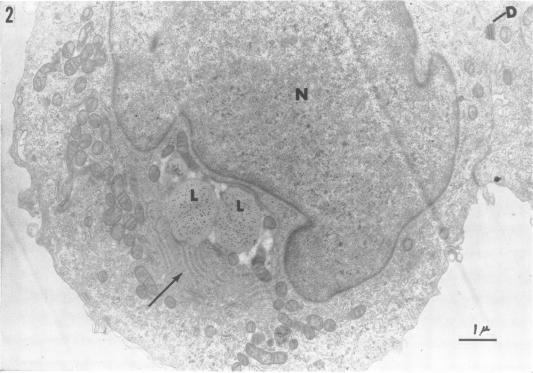

感染风疹病毒的猴肾细胞培养物的电子显微镜检查。

Electron microscopy of monkey kidney cell cultures infected with rubella virus.

Two rubella virus strains isolated in this laboratory were investigated in terms of their growth in LLC-MK(2) cell cultures and their effect on cell morphology. Rubella virus grew readily in LLC-MK(2) cells, but cytopathic effects of the virus were not observed in infected cultures. Such infected cultures can be subcultured indefinitely and continue to shed virus. Examination of rubella-infected cell cultures by electron microscopy showed the presence of annulate lamellae in the cytoplasm of 15% of the cells. No changes were evident in the nuclei. These membranous inclusions varied in complexity from parallel arrays of annulate lamellae to large lamellar structures of complex morphology. An occasional cell contained a crystal lattice structure in association with the lamellae. Larger inclusions, consisting of disorganized arrays of "unit" membranes, were also found. Uninfected cells were devoid of annulate lamellae, crystals, and complex membranous inclusions. No viruslike particles were observed in any part of the cells from infected cultures. The significance of the structures observed has not been determined.

对本实验室分离出的两株风疹病毒进行了研究,观察它们在LLC-MK(2)细胞培养物中的生长情况及其对细胞形态的影响。风疹病毒在LLC-MK(2)细胞中易于生长,但在感染的培养物中未观察到病毒的细胞病变效应。此类感染的培养物可无限传代并持续释放病毒。通过电子显微镜检查风疹感染的细胞培养物发现,15%的细胞胞质中存在环状片层。细胞核未见明显变化。这些膜性内含物的复杂程度各不相同,从平行排列的环状片层到形态复杂的大的片层结构。偶尔有细胞含有与片层相关的晶格结构。还发现了由“单位”膜无序排列组成的较大内含物。未感染的细胞没有环状片层、晶体和复杂的膜性内含物。在感染培养物的细胞任何部位均未观察到病毒样颗粒。所观察到的结构的意义尚未确定。